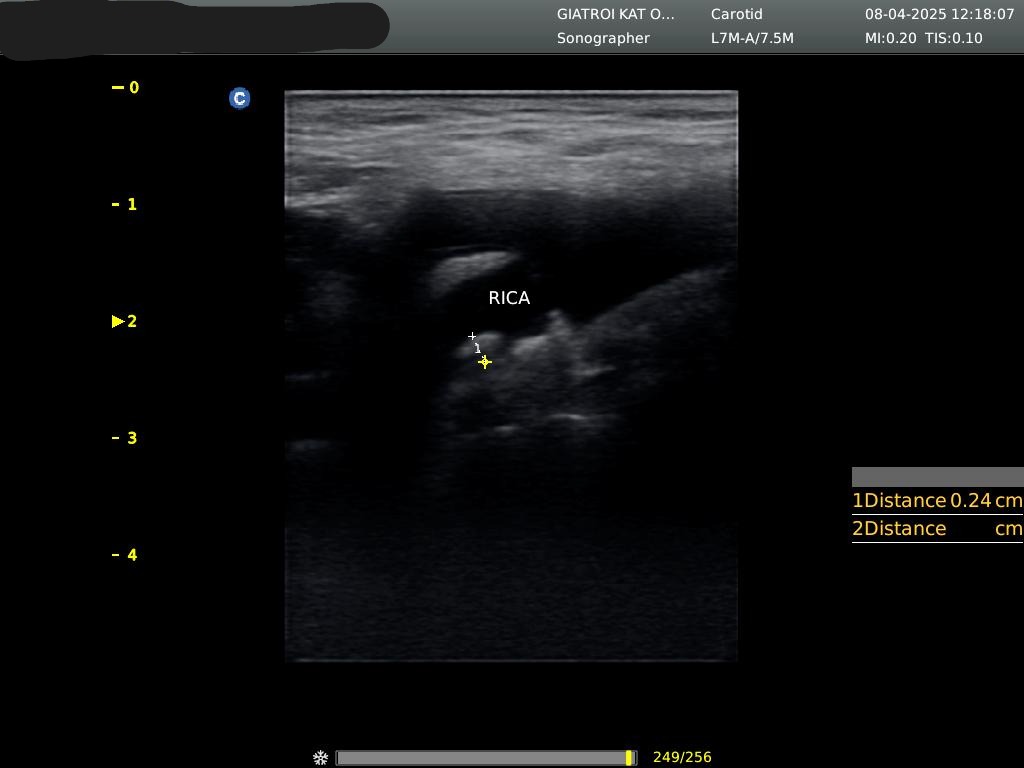

Τι είναι το triplex αγγείων και πότε χρειάζεται;

Το triplex είναι υπερηχογράφημα που απεικονίζει τη ροή του αίματος σε φλέβες και αρτηρίες. Χρησιμοποιείται για τον έλεγχο θρόμβωσης, στενώσεων, αποφράξεων ή ανευρυσμάτων σε άνω και κάτω άκρα, καρωτίδες και κοιλιακή αορτή.